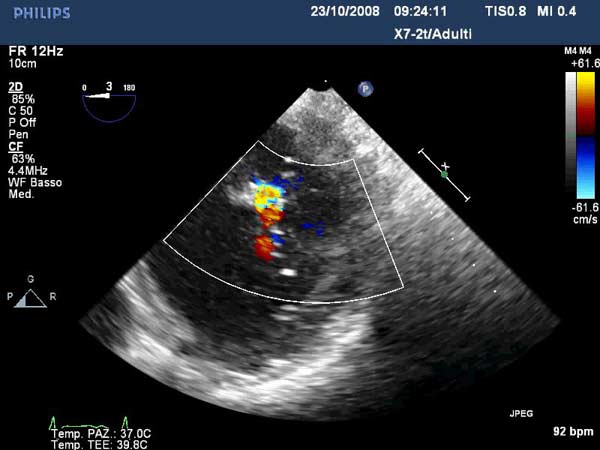

Percutaneous mitral repair using the MitraClip® system (Evalve, Inc., Menlo Park, CA USA) is a method derived from the double orifice open heart surgical technique. According to this technique, mitral regurgitation (MR) is treated by suturing the free edges of the opposing leaflets at the site of regurgitation. The surgical procedure was introduced in clinical practice more than 15 years ago [1], and has proven early efficacy and durability in various anatomic and functional lesions. The MitraClip system reproduces the surgical procedure using a clip to join the opposing leaflets at the location of the MR origin [2]. The system includes the MitraClip device (Figure 1) and a sophisticated delivery system (Figure 2) which is used under echo guidance.

In absence of controlled clinical trial data which are forthcoming from the EVEREST II randomized study, the indications for the MitraClip therapy are currently based on registry experience and will evolve as the technique improves, experience is growing and the data to demonstrate efficacy and safety becomes available. At this time, the best indication for the MitraClip therapy is for symptomatic patients with clinically significant functional or degenerative MR who are at high or increased risk for open heart surgery. From a pure technical standpoint, the procedure so far has only been demonstrated in a subgroup of patients with specific anatomical characteristics which are summarized below and shown in Figure 3. Anatomic suitability is assessed by transesophageal echocardiography, and mitral regurgitation should originate from the central portion of the valve involving the A2-P2 segments, since the device is not ideal to work in the commissures at this time; the mechanism of MR can be either a prolapse/flail or MR due to restricted leaflet motion unrelated to rheumatic disease; the separation between the two leaflets at the site of regurgitation should be limited; severe annular dilatation and/or severe calcification should be absent or is relevant. In case of flail, the flail segment width should be less than 15 mm, and the flail gap less than 10 mm. Figure 4 is a 3D echo image of a patient with posterior leaflet prolapse selected for MitraClip therapy. In case of functional MR, the leaflets should have a minimal residual tissue available for coaptation with the MitraClip device. Figure 5 shows 2D color Doppler jet extension over the coaptation line at TEE short axis transgastric view, while Figure 6 shows the tenting area and the coaptation depth of a patient undergoing MitraClip implant.